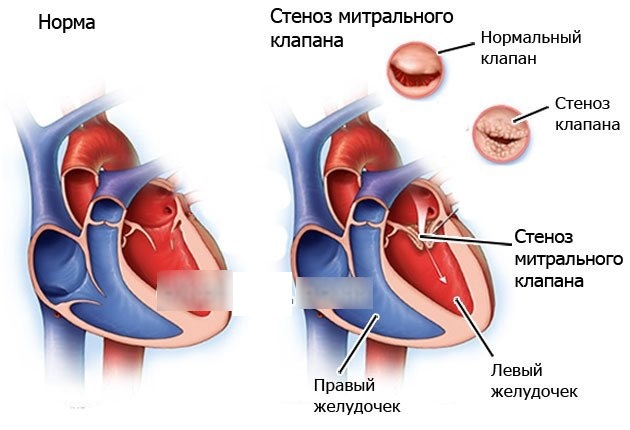

Фотографии и информация о приобретенных пороках сердца